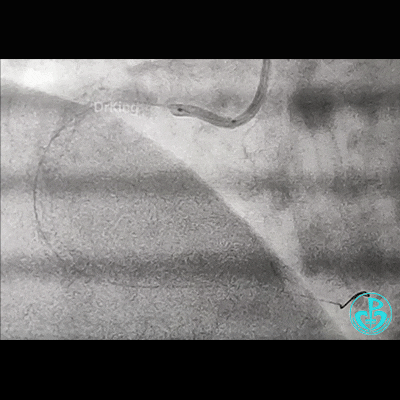

开始后扩,3.5×15mm后扩球囊不能进入近端支架口,GC系统飞出!故事开始。

重进导丝,比较顺利!3.5×15mm球囊仍不能通过支架近段!再进一根导丝,还不行!

考虑导丝可能从支架钢梁外进入,故调整GC,把两根导丝均Knuckle进入,再进球囊!不行!

因右锁骨下动脉迂曲打弯,GC张力过高,尝试GC深插,有阻力,不敢粗暴,稍微提出到开口,则立即飞出!